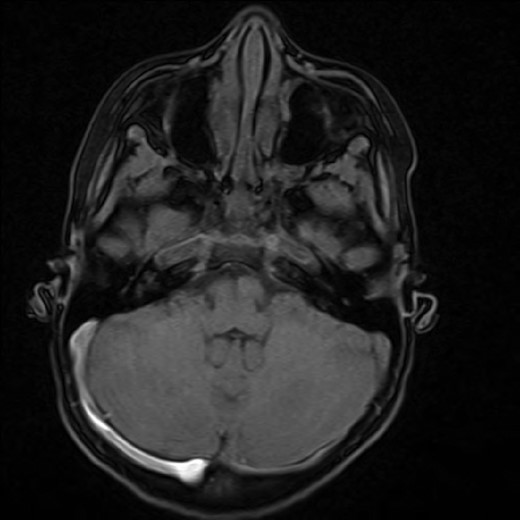

We present a very rare case of indirect cavernous carotid fistula (CCF) in a 12-year-old girl. Indirect CCF is extremely rare in the paediatric population. A 12-year-old girl presented with a 7-month history of frontal headaches and intermittent left-sided proptosis. On examination, she had dilated and engorged scleral veins on the left eye, mild dysdiadochokinesia and past pointing on the left side. A brain computer tomography with contrast, brain magnetic resonance imaging (MRI) and interventional radiography (IR) cerebral angiogram confirmed the diagnosis of CCF. The CCF was embolized and a follow-up brain MRI and an IR cerebral angiogram were conducted over the course of 8 months that revealed no evidence of residual CCF. CCF, though rare in the paediatric population, should be highly considered in the differential diagnosis when dilated scleral veins, proptosis and dysdiadokinesis are present in the clinical setting. Prompt treatment has good prognostic results.

Spontaneous cavernous carotid fistula (CCFs) are less common than traumatic CCFs and are quite a rare entity in children. Their presentation widely varies, and diagnosis is commonly delayed due to late presentation to the hospital. Most CCFs are not life threatening; however, it is essential that CCFs be not overlooked in the paediatric population especially when dilated scleral veins, persistent headaches, proptosis and dysdiadochokinesis are present (Fig. 1).

A 12-year-old girl presented with a 7-month history of frontal headaches and intermittent left-sided proptosis. On examination, she had dilated and engorged scleral veins on the left eye (evident on inspection), mild dysdiadochokinesia and past pointing on the left side. A brain computed tomography (CT) with contrast showed an enlarged left superior ophthalmic vein and a prominent left cavernous sinus. An interventional radiography (IR) cerebral angiogram under general anaesthesia was performed, which revealed evidence of an indirect CCF fed by ophthalmic branches of the left internal carotid artery and filling from multiple ethmodial branches of the distal internal maxillary artery. From the fistula, the ophthalmic vein was markedly hypertrophied and drained the cavernous sinus anteriorly. The fistula was also feeding from the right side through ethmodial branches into the right cavernous sinus and across to the left cavernous sinus (Fig. 2).